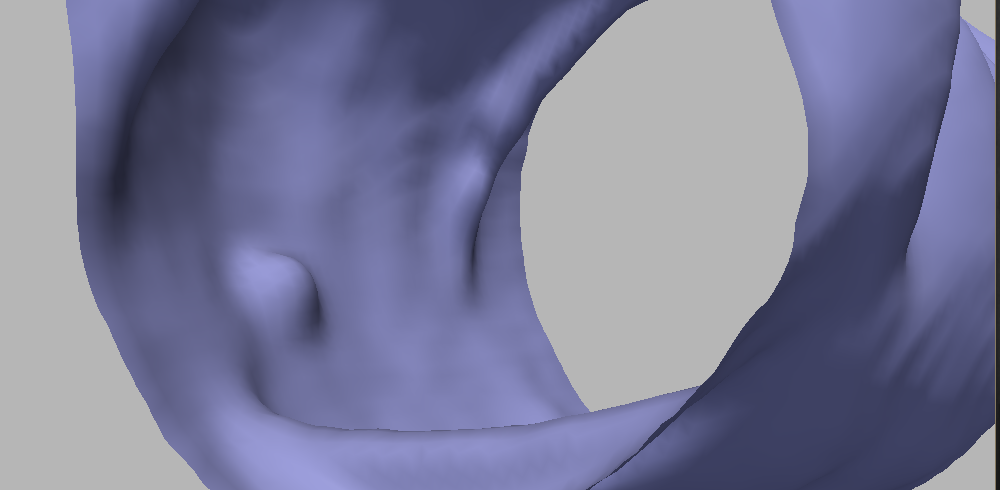

The first modification is inspired by the exponent of the affine motions in dimension , and yields to the following curvature motion equation:

Figure 7 shows the result after a few iterations; comparing to Figure 5, it can be readily seen that this motion achieves a better trade-off in terms of noise reduction and polyp preservation. Figure 8 evidences the difference with a comparative image: the result of the motions by and are shown in gray and in orange, respectively. On the polyp protrusion, the orange surface is above the gray surface, while the opposite is observed in the surrounding area. This shows that the evolution by leads to better polyp enhancement.

The final motion then becomes

This proposed evolution keeps all the advantages of the motion by and in addition, the polyps are flattened slower, so at the end the obtained surface is smooth and the polyps are still outstanding.